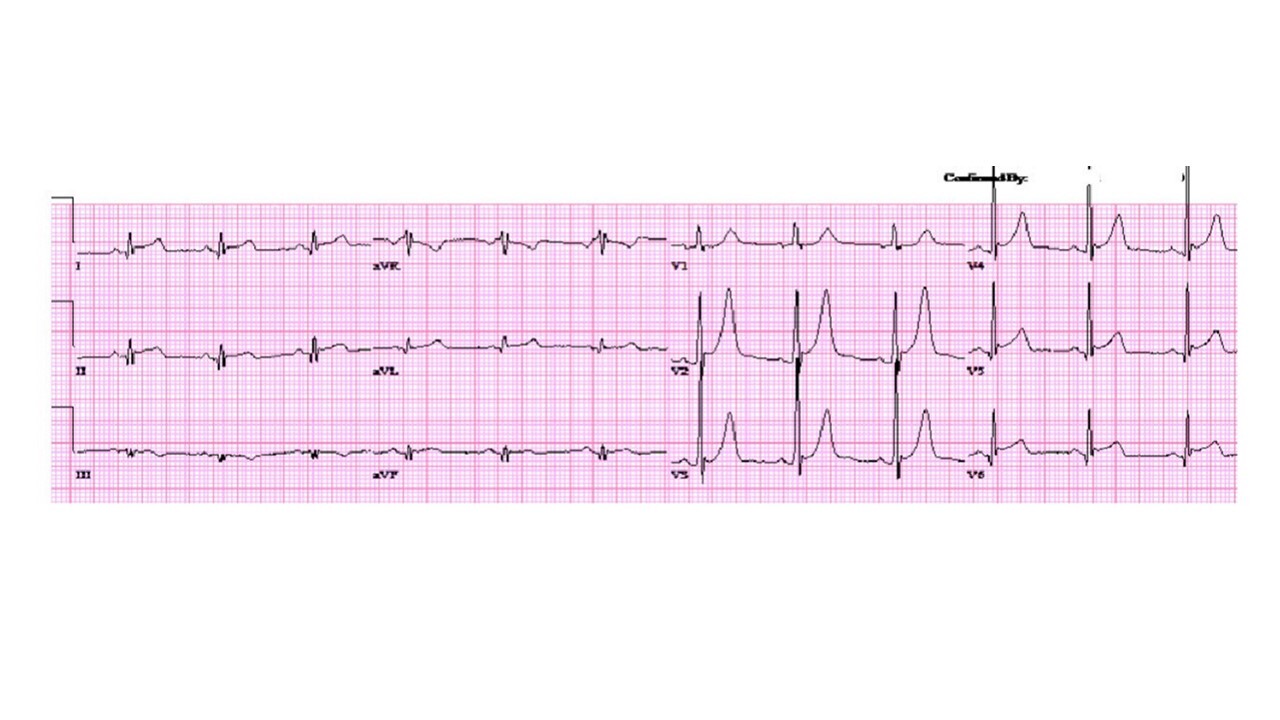

10

LBBB